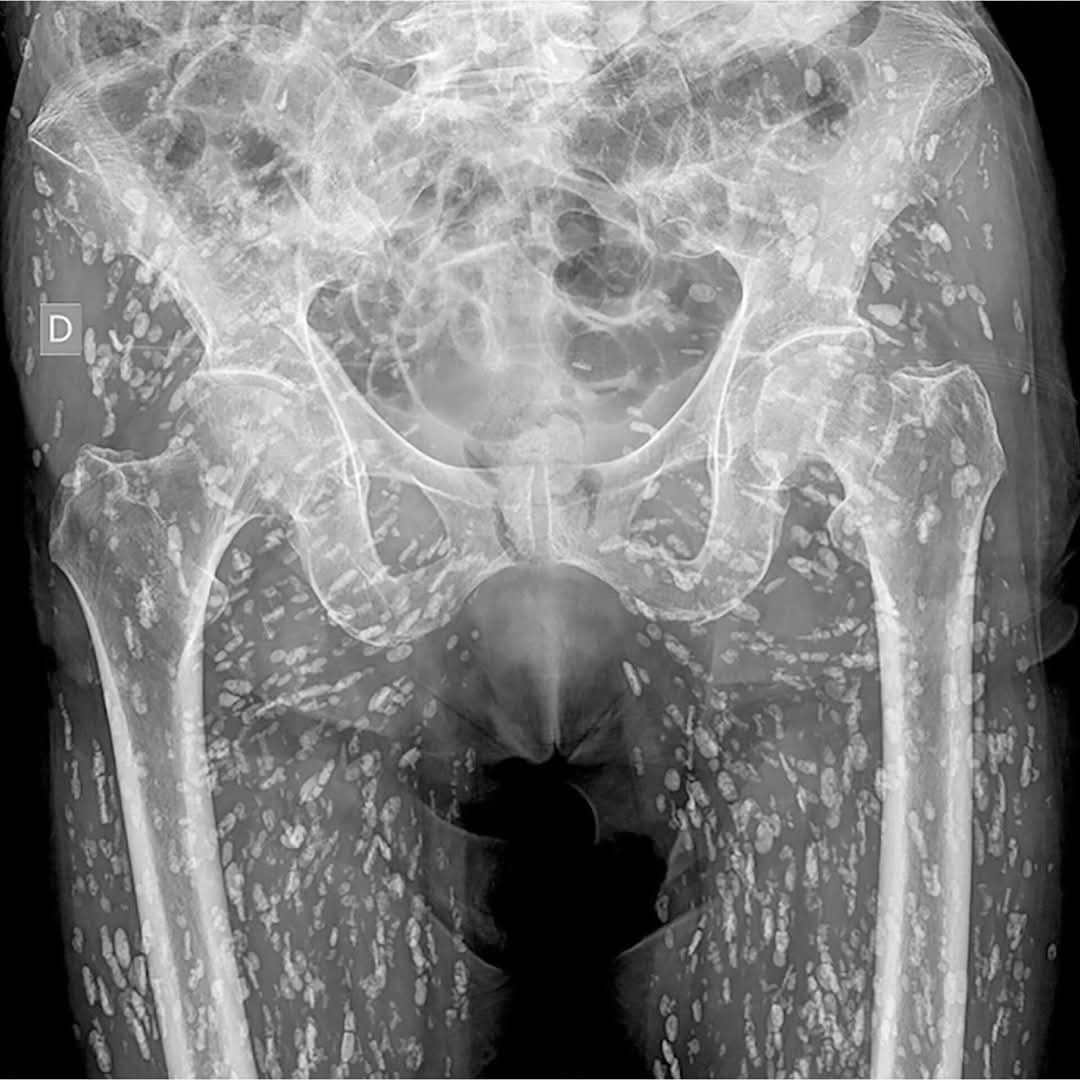

根據《Khaosod》報導,一位曾任X光助理的網友在社群平台分享,有名婦人前來照X光,當影像呈現時,從髖部到腿部竟布滿了密密麻麻的詭異陰影。放射科醫師仔細檢視後,震驚指出這些白點竟然全是寄生蟲!該患者可能因長期食用生食、生肉,不慎吞下蟲卵或幼蟲。現場醫護人員聽聞後紛紛起雞皮疙瘩,不斷以酒精消毒雙手。

專家提醒,生食容易感染絛蟲病,若體內有寄生蟲,可能出現持續性飢餓感、腹部不適、消化問題、噁心想吐,以及腹瀉或便祕等症狀,甚至導致體重減輕。預防之道就是確保肉類完全煮熟,並注意生熟食分開處理。